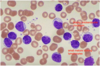

Acute Myeloid Leukemia

Acute Myeloid Leukemia

Acute Myeloid Leukemia

Acute Promyelocytic Leukemia (M3 AML)

M4/5 AML